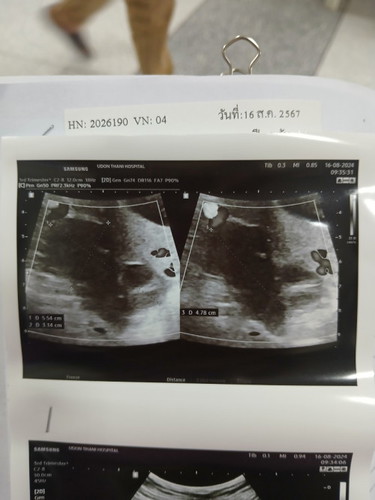

มีใครตั้งครรภ์อยู่แล้วแล้วตรวจเจอว่า มีซีสต์ที่รังไข่ปีกขาวบ้สงไหมค่ะ อันตรายไหม กังวลจัง พอดีเมื่อวานนี้คุณหมออัลตร้าซาวด์ ดูวันที่ครบกำหนดคลอด แล้วคุณหมอก็เลยเห็นอยู่ทางปีกด้านขวา แต่ไม่รู้ว่าเป็นซีสต์ชนิดไหน คุณหมอก็เลยส่ง ให้ไปตรวจ กับหมอ มะเร็ง ก็เลยงงว่า แค่เพิ่งเจอว่าเป็นซีสต์สรุปได้เลยหรอว่าเป็นมะเร็ง ก็งง คุณหมอก็ไม่ได้แจ้งอะไรแค่บอกว่าให้หมอเฉพาะทางดูว่า เป็น ชนิดไหนแค่นั้น